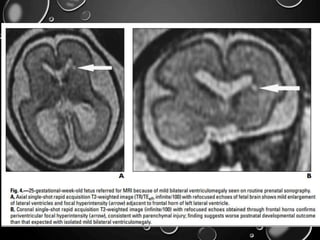

VENTRICULOMEGALY

• MOST COMMON; SONOGRAPHY. - ATRIAL WIDTH GREATER THAN 10

MM MEASURED AT THE POSTERIOR MARGIN OF THE GLOMUS OF THE

CHOROID PLEXUS ON AN AXIAL PLANE THROUGH THE THALAMI .

• DESPITE THE GROWTH OF THE SURROUNDING BRAIN, THE ATRIAL

DIAMETER IS RELATIVELY CONSTANT FROM 15 TO 35 WEEKS

’GESTATION, SO THE LATERAL VENTRICLES APPEAR

PROPORTIONATELY LARGER EARLY IN GESTATION .

• ASSOCIATED STRUCTURAL ABNORMALITIES INCLUDE NEURAL TUBE

DEFECTS, AGENESIS OF THE CORPUS CALLOSUM, DANDY-WALKER

SYNDROME, HOLOPROSENCEPHALY, CORTICAL MALFORMATIONS,

INTRACRANIAL HEMORRHAGE, AND PORENCEPHALY

• INCLUDING AGENESIS OF THE CORPUS CALLOSUM,

CORTICAL MALFORMATIONS, PERIVENTRICULAR

HETEROTOPIA, PERIVENTRICULAR LEUKOMALACIA,

MULTICYSTIC ENCEPHALOMALACIA, AND INTRACRANIAL

HEMORRHAGE.

• PERIVENTRICULAR WHITE MATTER INJURY MAY MANIFEST

AS FOCAL PERIVENTRICULAR T2 HYPERINTENSITY, FOCAL

DEFECTS IN THE GERMINAL MATRIX, SUBTLE IRREGULARITY

OF THE VENTRICULAR MARGIN, OR LARGE AREAS OF

ABNORMAL SIGNAL IN THE DEVELOPING WHITE MATTER

AND OVERLYING CORTEX. MAY OR MAY NOT BE

ASSOCIATED WITH VOLUME LOSS.

• HEMORRHAGE IS USUALLY DETECTED AS FOCI OF

T1HYPERINTENSITY AND T2 HYPOINTENSITY IN THE

GERMINAL MATRIX, VENTRICLES, OR BRAIN PARENCHYMA.

• BLOOD IN THE VENTRICLES MAY LAYER OR FORM A

DISCRETE CLOT.